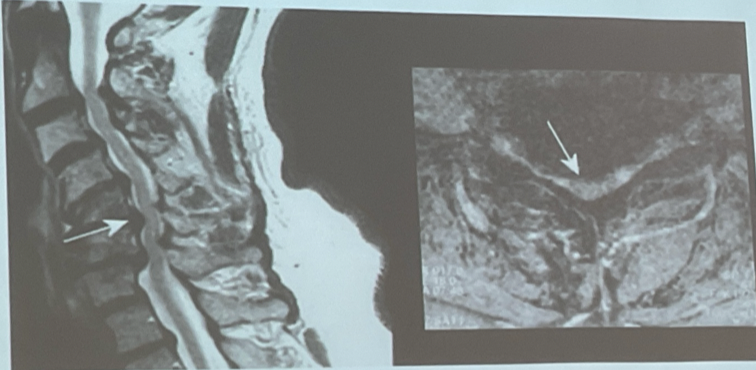

RM para descartar lesión estructurales

Canal cervical estrecho: DXDX

ELA: Hiperintensidades del tracto corticoespinal